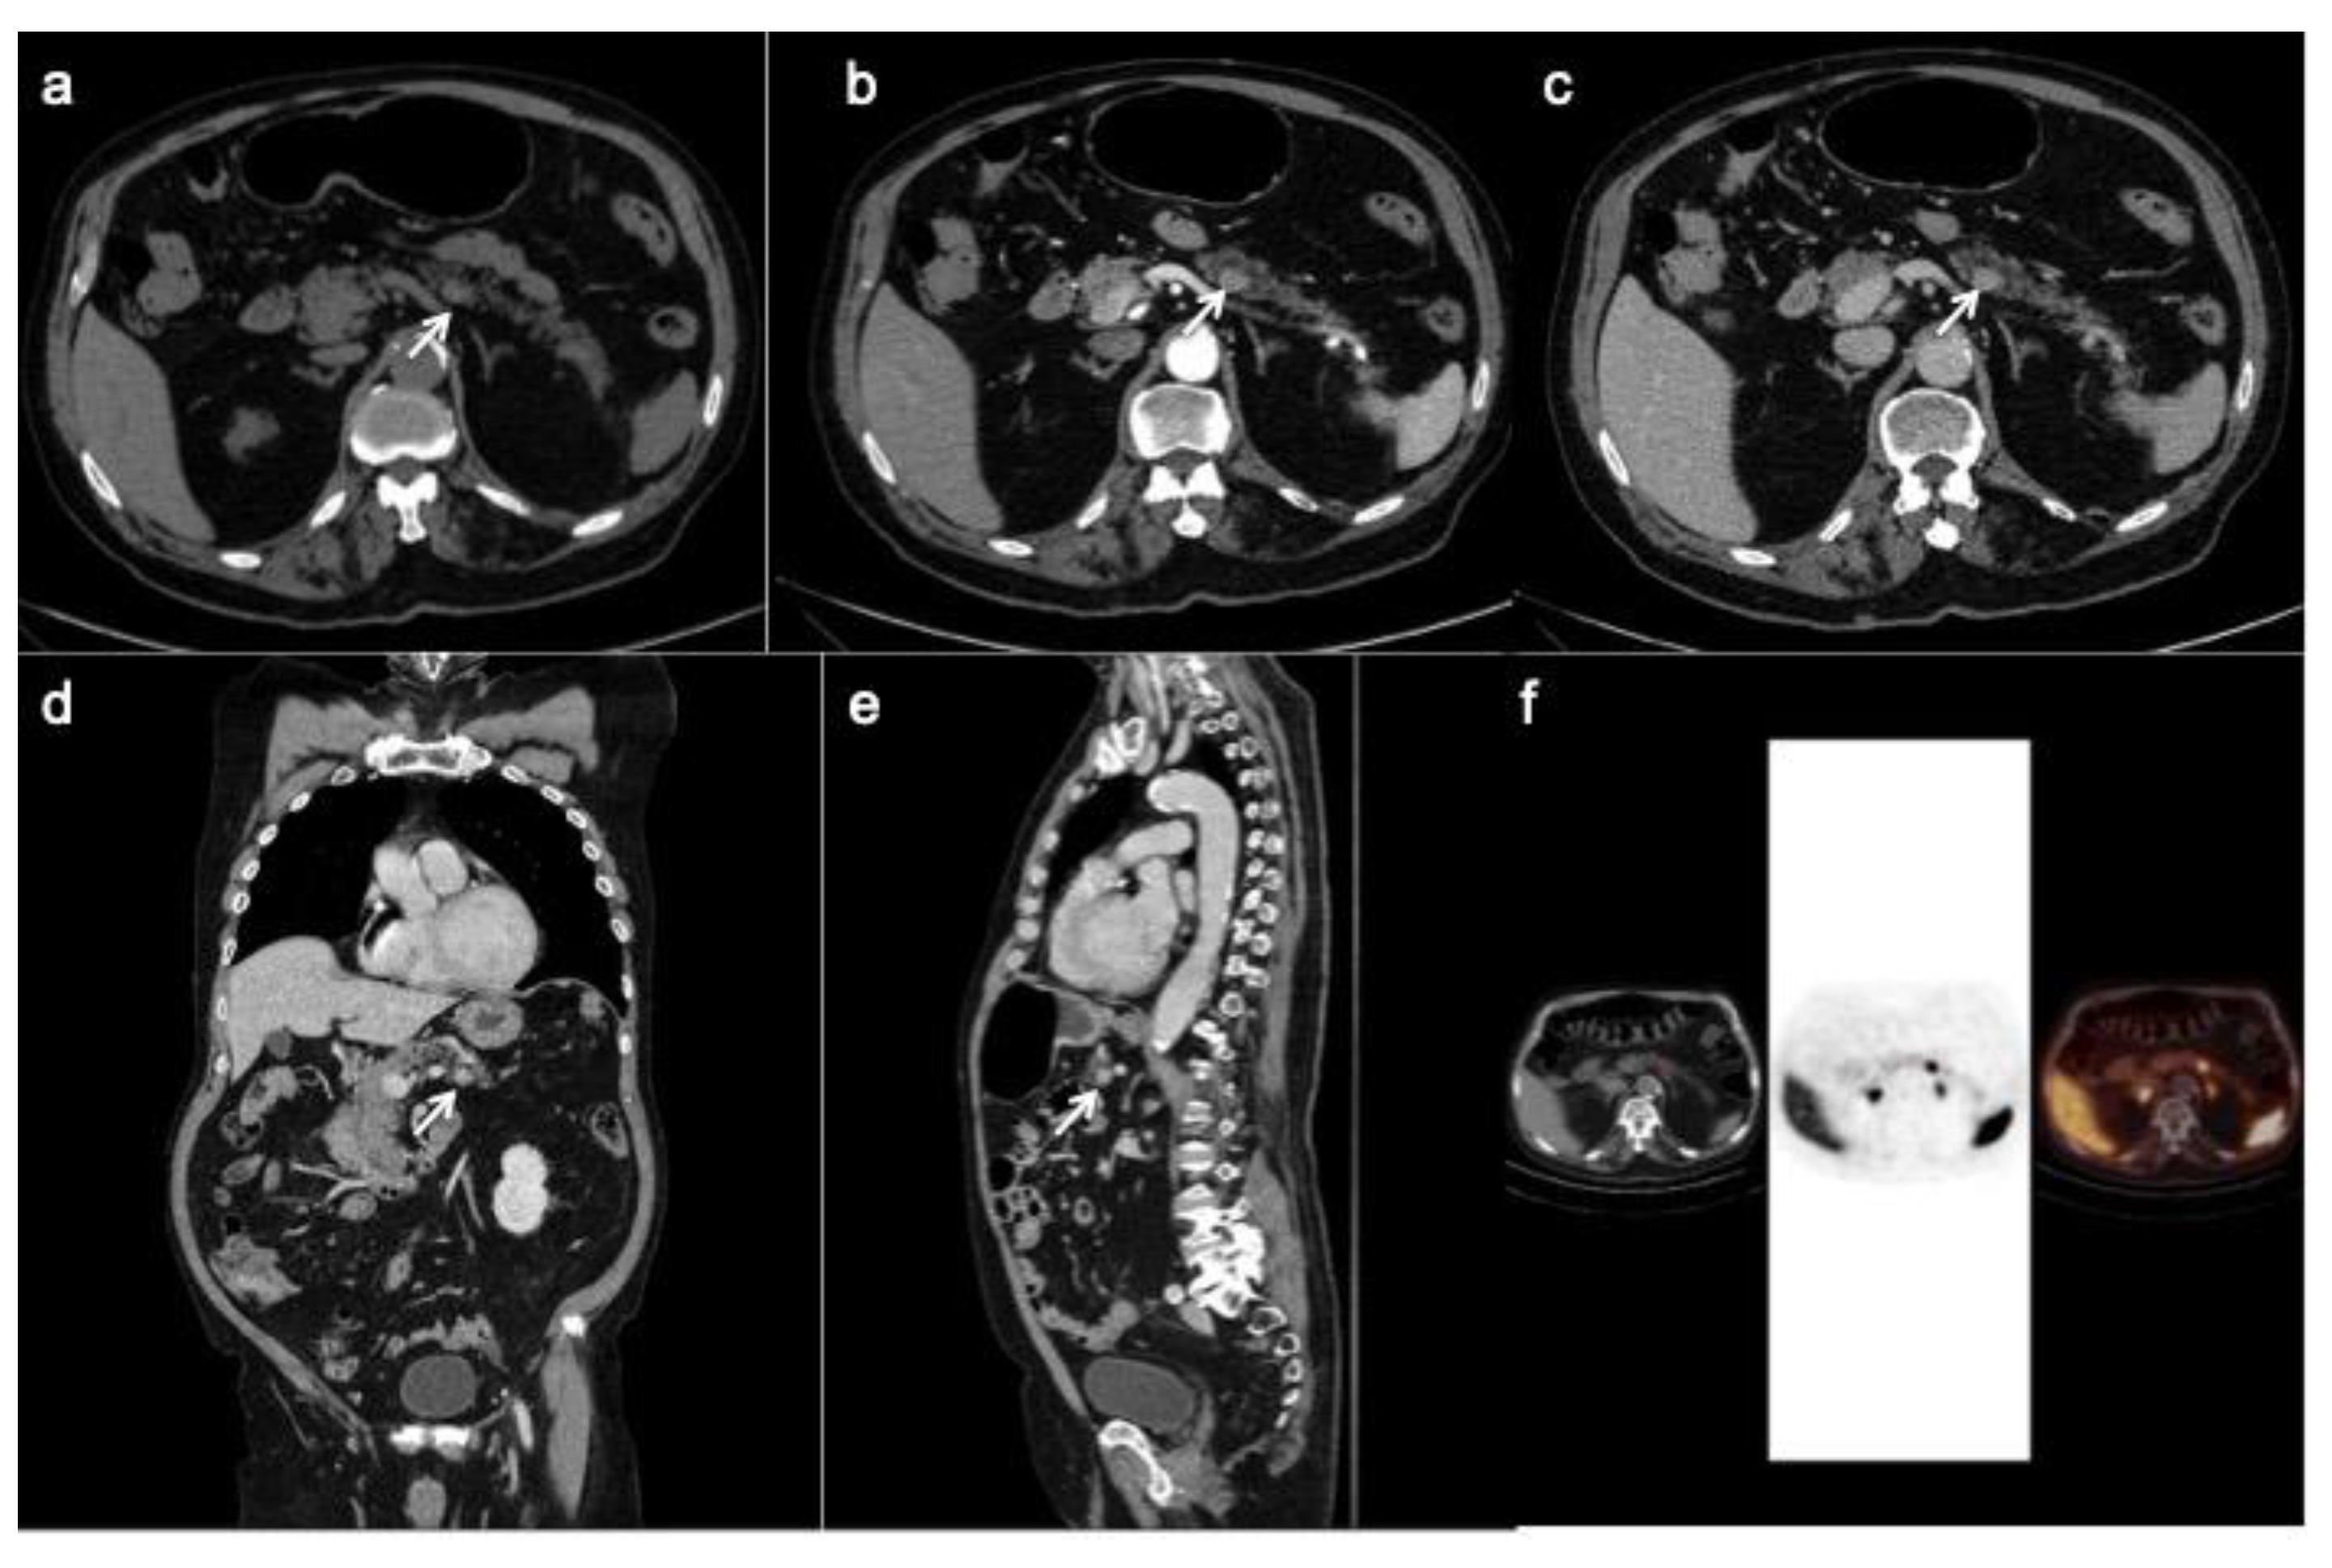

Figure 2.

Patient with liver metastases from poorly differentiated pancreatic neuroendocrine carcinoma. CT images in the transverse plane during the basal (a), the arterial (b) and portal (c) phases show a large mass developed in the pancreatic tail with atypical hypo-enhancing pattern (arrow). This lesion is associated with multiple liver metastases (arrowheads) that appear hypodense with rim enhancement during arterial phase (b). According to the poorly differentiated tumor feature, FDG PET/CT (e,f) shows high uptake in pancreatic lesion while Somatostatin Receptor Scintigraphy with 111-pentetrotide is negative (d).

PET/CT with 68-Gallio labeled SSA is the imaging method of choice for panNEN functional study. There are mainly three available SSAs showing no substantial differences in patients staging: 68-Ga-DOTANOC, 68-Ga-DOTATOC (Figure 5) and 68-Ga-DOTATATE. All of them are SSRT2 high-affinity tracers; only 68-Ga-DOTANOC proved to have an affinity for SSRT3.

Figure 5.

CT images (a–c) show a hyper-enhancing pancreatic nodule in the body/tail of the organ (arrows) well depicted on the coronal (d) and sagittal (e) reconstruction too. The 68-Ga-DOTATOC PET/CT (f) shows focal uptake in the pancreatic lesion.